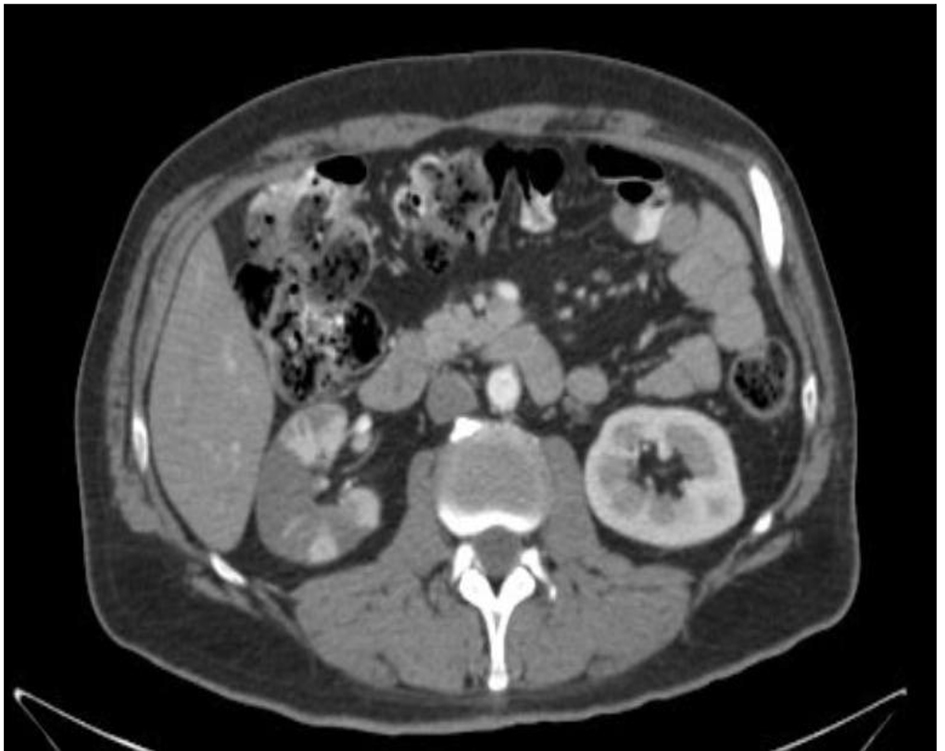

A 56-year-old man with medical history of hypertension and diabetes mellitus presented to emergency department with complaint of sudden onset of severe right lower abdominal pain for 1 day. History was negative for urinary symptoms, constipation or diarrhea, trauma to abdomen or alcohol abuse. Three weeks prior, he was admitted in intensive care unit for suicidal attempt with acetaminophen overdose. History was negative for fever, chills, joint pain, rashes or kidney stones. Vital signs in emergency department showed BP 145/74, HR 87/min, RR 16/min, and temperature 36.3 °C. Systemic examination was positive for mild tenderness at right lower abdomen and severe tenderness at right costovertebral angle. Chest exam was normal, cardiovascular exam revealed systolic murmur at the mitral area and patient said he was told to have murmur in the past. Initial lab tests revealed WBC 16,650, Hb 14.4 g/dL, and platelet 432,000. Urinalysis showed WBC 6 - 10, RBC 3 - 5, negative leukocyte esterase and nitrite. Liver function showed ALT 77, AST 116, LD 1,051 with normal bilirubin, albumin and INR. Liver function was probably deranged from recovering liver injury from acetaminophen overdose but LD was disproportionately high. Urine drug screen was negative. CT scan of abdomen with contrast showed striated appearance of the right kidney with hypoperfusion and wedge-shaped hypodensities throughout the kidney (Figs. 1 and 2). Given radiographic appearance, acute onset, and evidence of leukocytosis, pyelonephritis versus multifocal infarction were suspected. He was started on antibiotics for pyelonephritis. But the clinical picture was more favorable for kidney infarction due to absence of fever, urinary symptoms and normal urinalysis. Urine culture showed mixed flora. Ultrasound with Doppler study showed relative decrease in blood flow within the right peripheral renal cortex compared to the left and the study was negative for renal artery stenosis. Lactate dehydrogenase was elevated to 1,051 at admission, peaked at 2,049 and decreased to 733 at the time of discharge. Due to disproportionate rise of lactate dehydrogenase, renal infarct was the more likely cause. Electrocardiogram showed normal sinus rhythm with no evidence of atrial fibrillation. The patient developed fever during hospital stay and blood culture was positive for methicillin sensitive Staphylococcus auricularis. Transthoracic echocardiogram was normal, but due to persistent fever, transesophageal echocardiogram was done that showed no vegetation and showed trivial mitral and tricuspid regurgitation with normal left ventricular ejection fraction.

![]() Click for large image | Figure 2. CT scan of abdomen (cross-section view). |